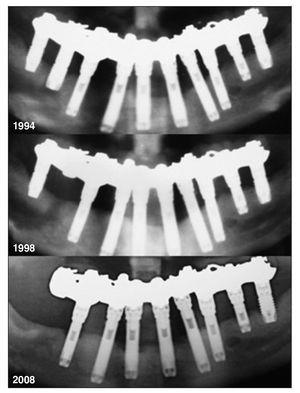

Figura 4 Resultado implantológico de la paciente hasta 18 años después de la colocación. Se perdió un implante entre 1994 y 1998. Entre 1998 y 2008 se perdieron dos implantes y se redujeron los niveles de hueso marginal.